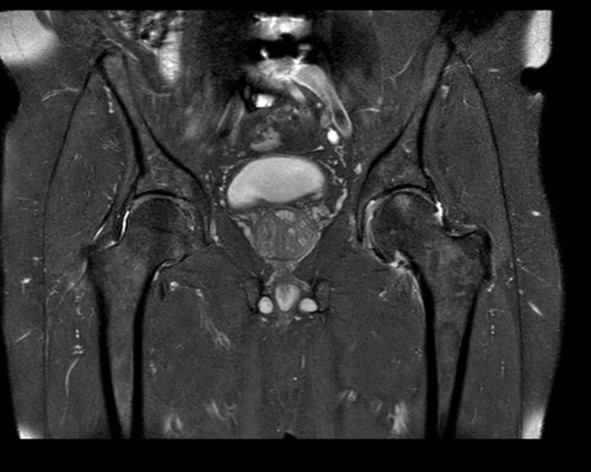

His radiographs in the clinic revealed left hip degenerative joint disease. Additionally, his pre-operative hip MRI revealed significant narrowing of the joint space and femoral head edema securing the diagnosis of degenerative joint disease. His exam was significant for limited internal rotation to no more than 5 degrees, a positive stinchfield test and an antalgic gait.

Radiographs are noted below. Pre-op, Post-op and intra-op radiographs are found below as well as the pre-op MRI.

Figure 4. Pre-operative MRI of the Pelvis demonstrating advanced left hip osteoarthritis as well as left femoral head edema.

Pre-op MRI:

Figure 4.